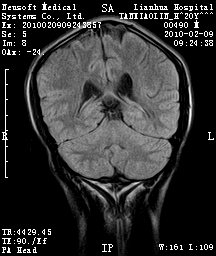

20岁男性患者,平时偶有头痛而无其他不适,现因持续头痛服药后无缓解而来院就诊。

松果体囊肿?

松果体区占位继发轻度脑积水?该患者有ct资料,我已发上。

考虑松果体囊肿。